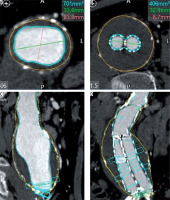

CT images were transferred to Vitrea (Vital Images, Inc., Minnetonka, Minnesota, United States) picture archiving and communication system (PACS) archive for initial assessment of aneurysm sack and stent graft location, which was performed using Vital Vitrea 6.7.2 software. For measurements of aneurysm length, maximum aneurysm diameter, aneurysm volume, lumen and thrombus volume the Vitrea Advanced aorta “stent graft planning“ protocol was used. Automated 3D segmentation by the software was performed, followed by manual adjustments to the centreline and outlines of the aneurysm and lumen in each slice where it was considered inaccurate. On average, the processing and evaluation of a single examination took 28.9 ± 2.3 min and 30.1 ± 0.8 min for the two radiologists accordingly. Maximum aneurysm diameter measurements were taken in orthogonal images perpendicular to the axis of aorta, measuring outer wall to outer wall (Figure 1). All measurements were recorded in millimetres (to the nearest 0.1 mm). Volumetric measurements included the portion of the abdominal aorta, aneurysm, and iliac arteries covered by stentgraft (Figure 2). The software computed the volume of aneurysm (including wall of aorta), lumen, and thrombus according to the outlines in millilitres (ml). The thrombus volume was calculated by subtracting the luminal volume from the AAA volume.